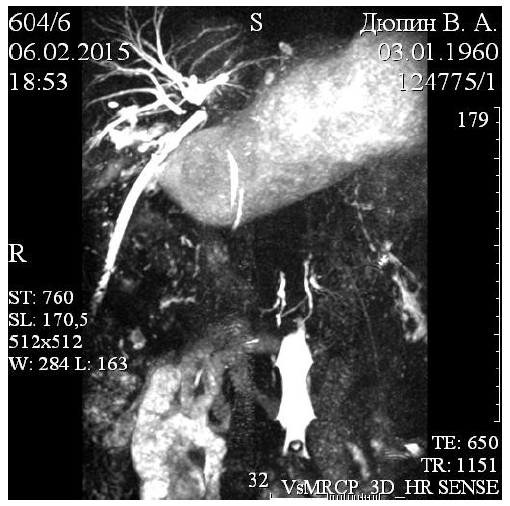

Рис. 2. МРТ-холангиография. Больной Д., 45 лет. Пересечение общего печеночного протока по уровню конфлюенса. Общий печеночный проток отсутствует на протяжении 35 мм. Контрольный дренаж в подпеченочном пространстве. Скоплений жидкости в брюшной полости не найдено

пространства отмечали выделение желчи более 300 мл в сутки, а при обследовании обнаруживали пересечение ВЖП (рис. 2), а у 6 – нарастающую механическую желтуху.